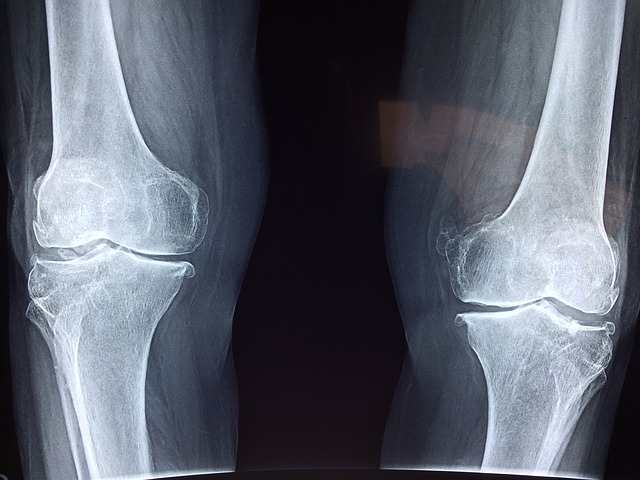

人體的骨質密度會在 30 歲時達到高峰,之後隨著年紀增長,骨量便會逐年減少。當骨質流失過多,原本緊密的骨頭變得多孔隙、單薄脆弱,就是所謂的「骨質疏鬆症」。若此時不小心跌倒、碰撞,或突然用力過猛,如打噴嚏,都有可能造成骨折;嚴重時,甚至會引起併發症,須要依賴他人照顧。內分泌及糖尿科專科張偉成醫生,將在下文為大家講解治療骨質疏鬆的辦法。